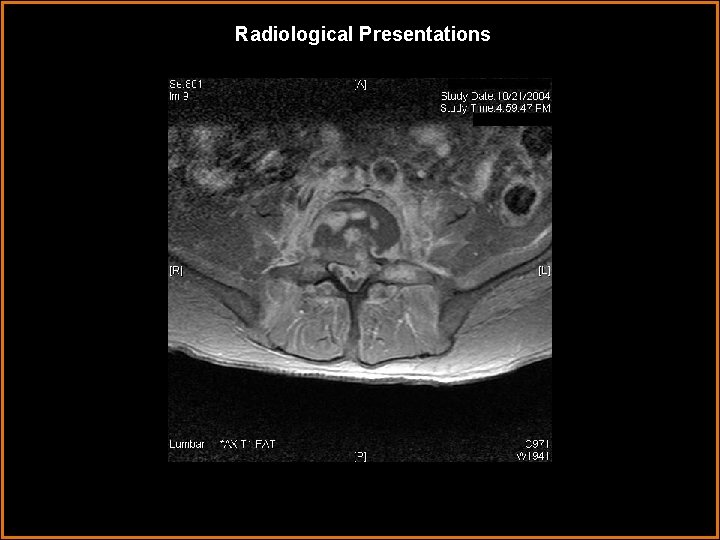

Findings and Differentials Findings: The L 4 -5 disc space is narrow and shows

Findings and Differentials Findings: The L 4 -5 disc space is narrow and shows increased T 2 signal intensity within the disc. There is erosion of the inferior L 4 and superior L 5 end plates with enhancement of the associated vertebral bodies after contrast. The paravertebral soft tissues enhance and extend through the foramina into the epidural space compressing thecal sac. Differentials: • Discitis with associated osteomyelitis and intraspinal extension • Intraspinal abscess extending into the vertebral bodies

Diagnosis Changes consistent with L 4 -5 DISCITIS. Inflammatory changes extend into the vertebral

Diagnosis Changes consistent with L 4 -5 DISCITIS. Inflammatory changes extend into the vertebral bodies, paravertebral, and epidural regions compressing thecal sac. CT guided biopsy with aspiration for culture is recommended.